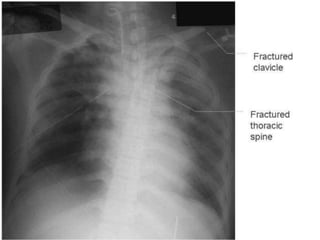

CXR